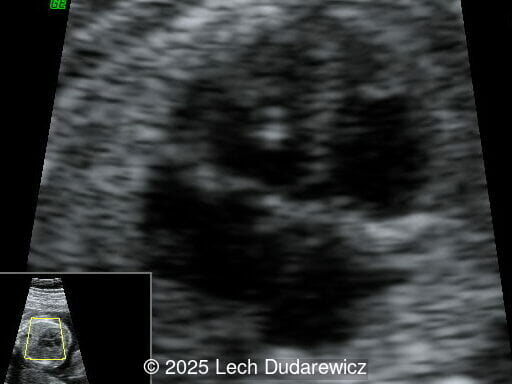

A 41-year-old secundigravida with a non-contributive medical history was referred for evaluation due to abnormal findings on a routine fetal ultrasound. Gestational age based on fetal biometry was estimated at 22 weeks.

We present a case of Campomelic Dysplasia.

Ultrasound revealed a single live fetus with 46,XY karyotype. Biometric measurements demonstrated discrepancies with the femur and tibia length lagging significantly at 19 weeks and notable shortening and bowing of the femur, tibia, and fibula. The findings were consistent with skeletal dysplasia.